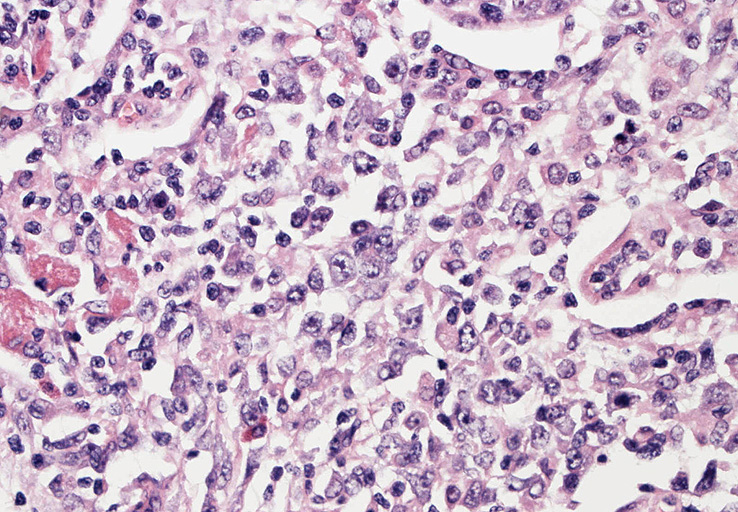

EBUS-GS(ガイドシース併用気管支腔内超音波断層法)による肺生検組織病理所見.

血管周囲性に大型類円形核や不整形核をもつ腫瘍細胞がシート状密に浸潤増殖している. Mitosisが多く認められる.細血管閉塞や破壊の所見がある.

間質にもシート状の腫瘍細胞浸潤がある. 大小 pleomorphicな傾向.(A, B). necrosisが認められる(C). 細気管支上皮直下まで密な浸潤あり, 小型リンパ球が混在している.(D)

血管中心性浸潤. 障害された血管内に血栓が形成されている.CD20陽性細胞がシート状密に浸潤, CD3陽性T細胞が多く混在している. EBER-ISH陽性 EBV感染細胞が多数認められ, >50 hpf, 定義より Grade3となる. 陽性細胞のサイズは大小さまざまであることに注意. Lymphomatoid granulomatosisの病態(WHO5thの診断では EBV-positive diffuse large B-cell lymphomaになる)をとっているが MTX-associated LPDの一型とするべき症例かもしれません.